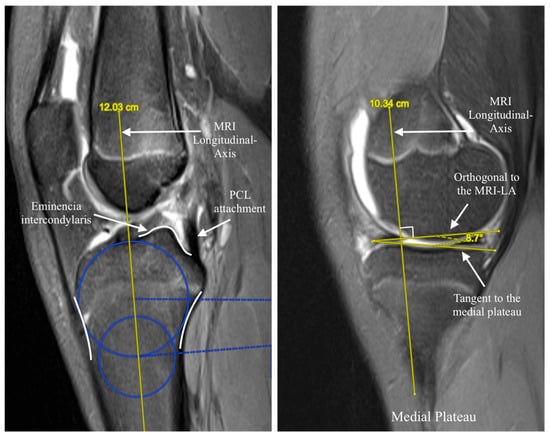

2.2. Measurement Methods